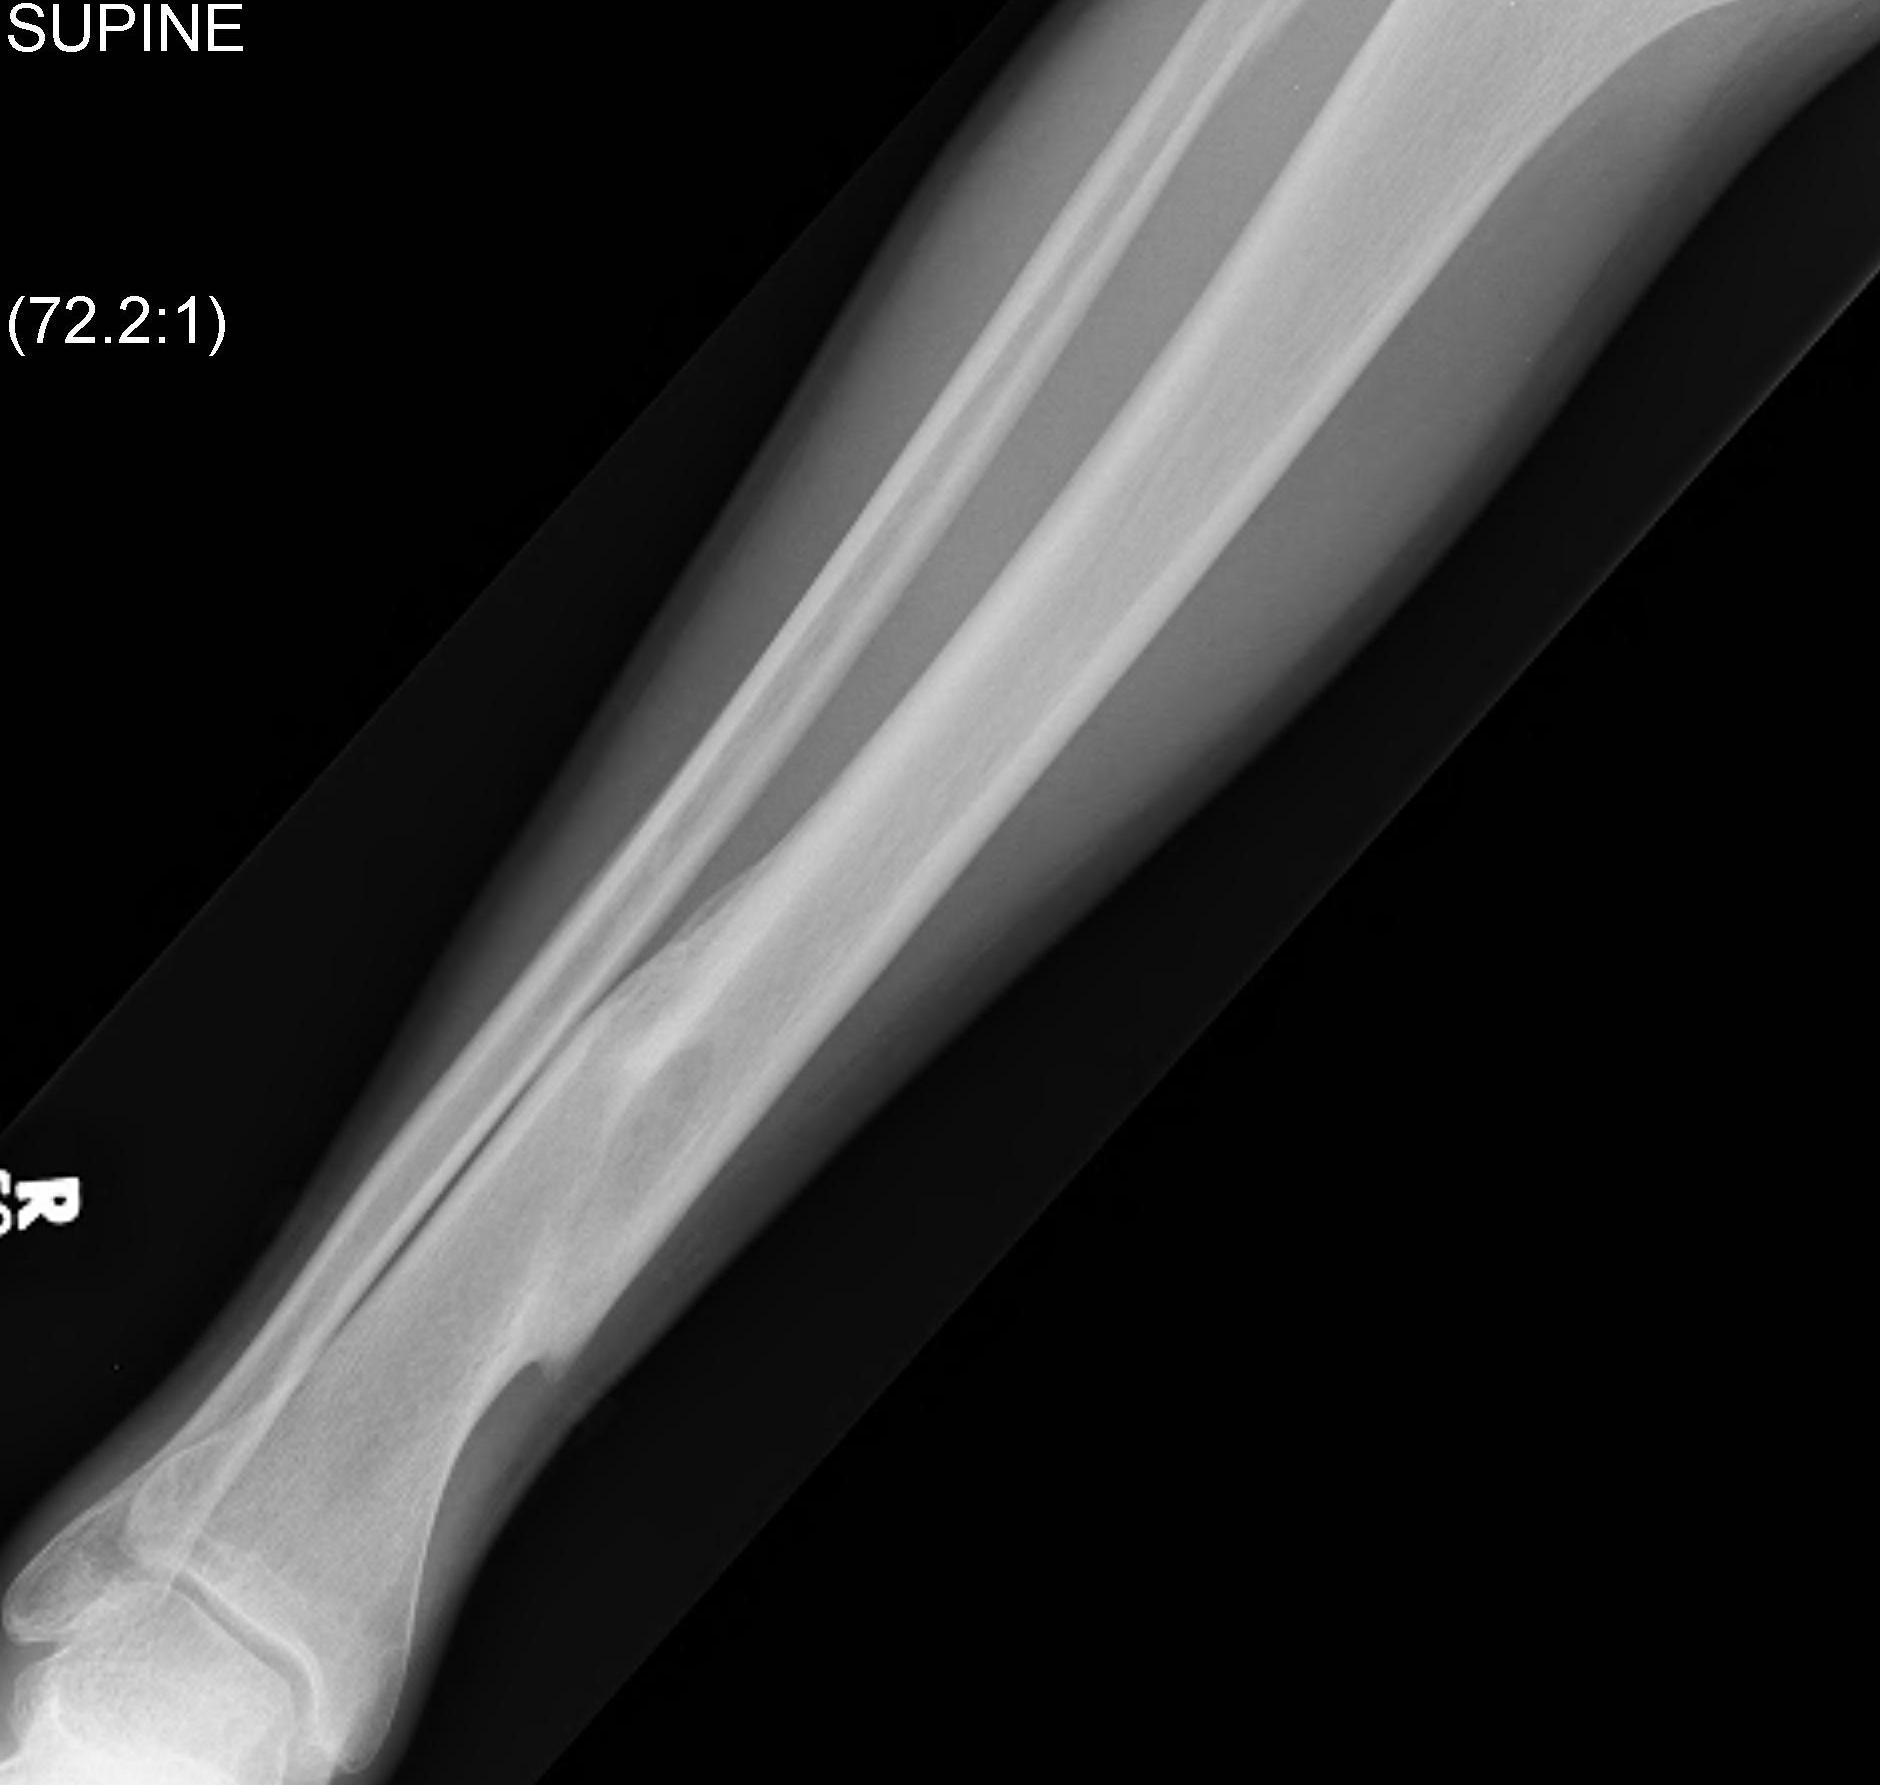

Technique

Consider semi-extended suprapatella nail

- easier to reduce fracture

- easier to get AP and lateral fluoroscopy

Most important is to centre guide wire over talus

- in lateral and AP

- use finger reduction tools and pass across fracture site to exact centre in AP and lateral